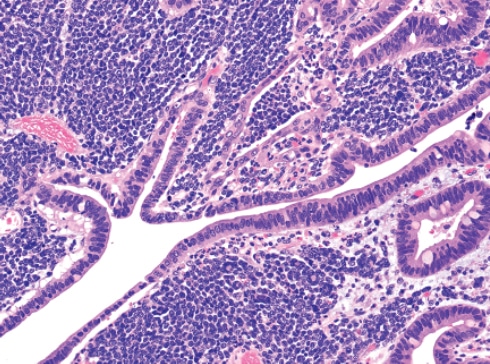

Featuring more than 1,000 high-resolution color graphics, Digestive System Tumours, the first volume of the fifth edition of the WHO series known as the Blue Books, brings a noticeable improvement in image quality and graphic design over the fourth edition, published in 2008. The book’s two-column layout, replacing the former three-column design, allows for enlarged images throughout. And this book is the first to be produced in both a print version and an online subscription version that includes whole-slide imaging.

The fourth edition of the WHO series set a whole new standard and raised the bar considerably from the third edition, Dr. Cree says. “And we are honestly trying to do the same with the fifth edition.” The new online subscription feature, for example, is intended not only to make user access easier but also to show significantly more content. “We have a whole-slide image for each diagnosis in the book. Whole-slide images allow us to get an overview of the entire section of the slide right down to the individual cells and see what is going on.” In addition, each paper in the book has a direct online link to the evidence that underpins the paper, he notes.

Pathologists learn so much from their exposure to illustrations, he says, and high-quality graphics have always been a feature of the WHO Blue Books. “When you collect world experts together and they all have their archives of gross photographs and microscopic slides, you can produce the best examples and most classic illustrations of the features.”

Now, the incorporation of digital slides will allow an interactive experience for the reader, who will be able to look at not just a single snapshot, such as would appear in a book, but also different magnifications that can be examined more comprehensively. This capability has become practical only in the past few years, Dr. Klimstra says. The WHO has learned from the experience of PathPresenter, which has created an educational portal for digital slides that is now an entirely new feature of the WHO series.